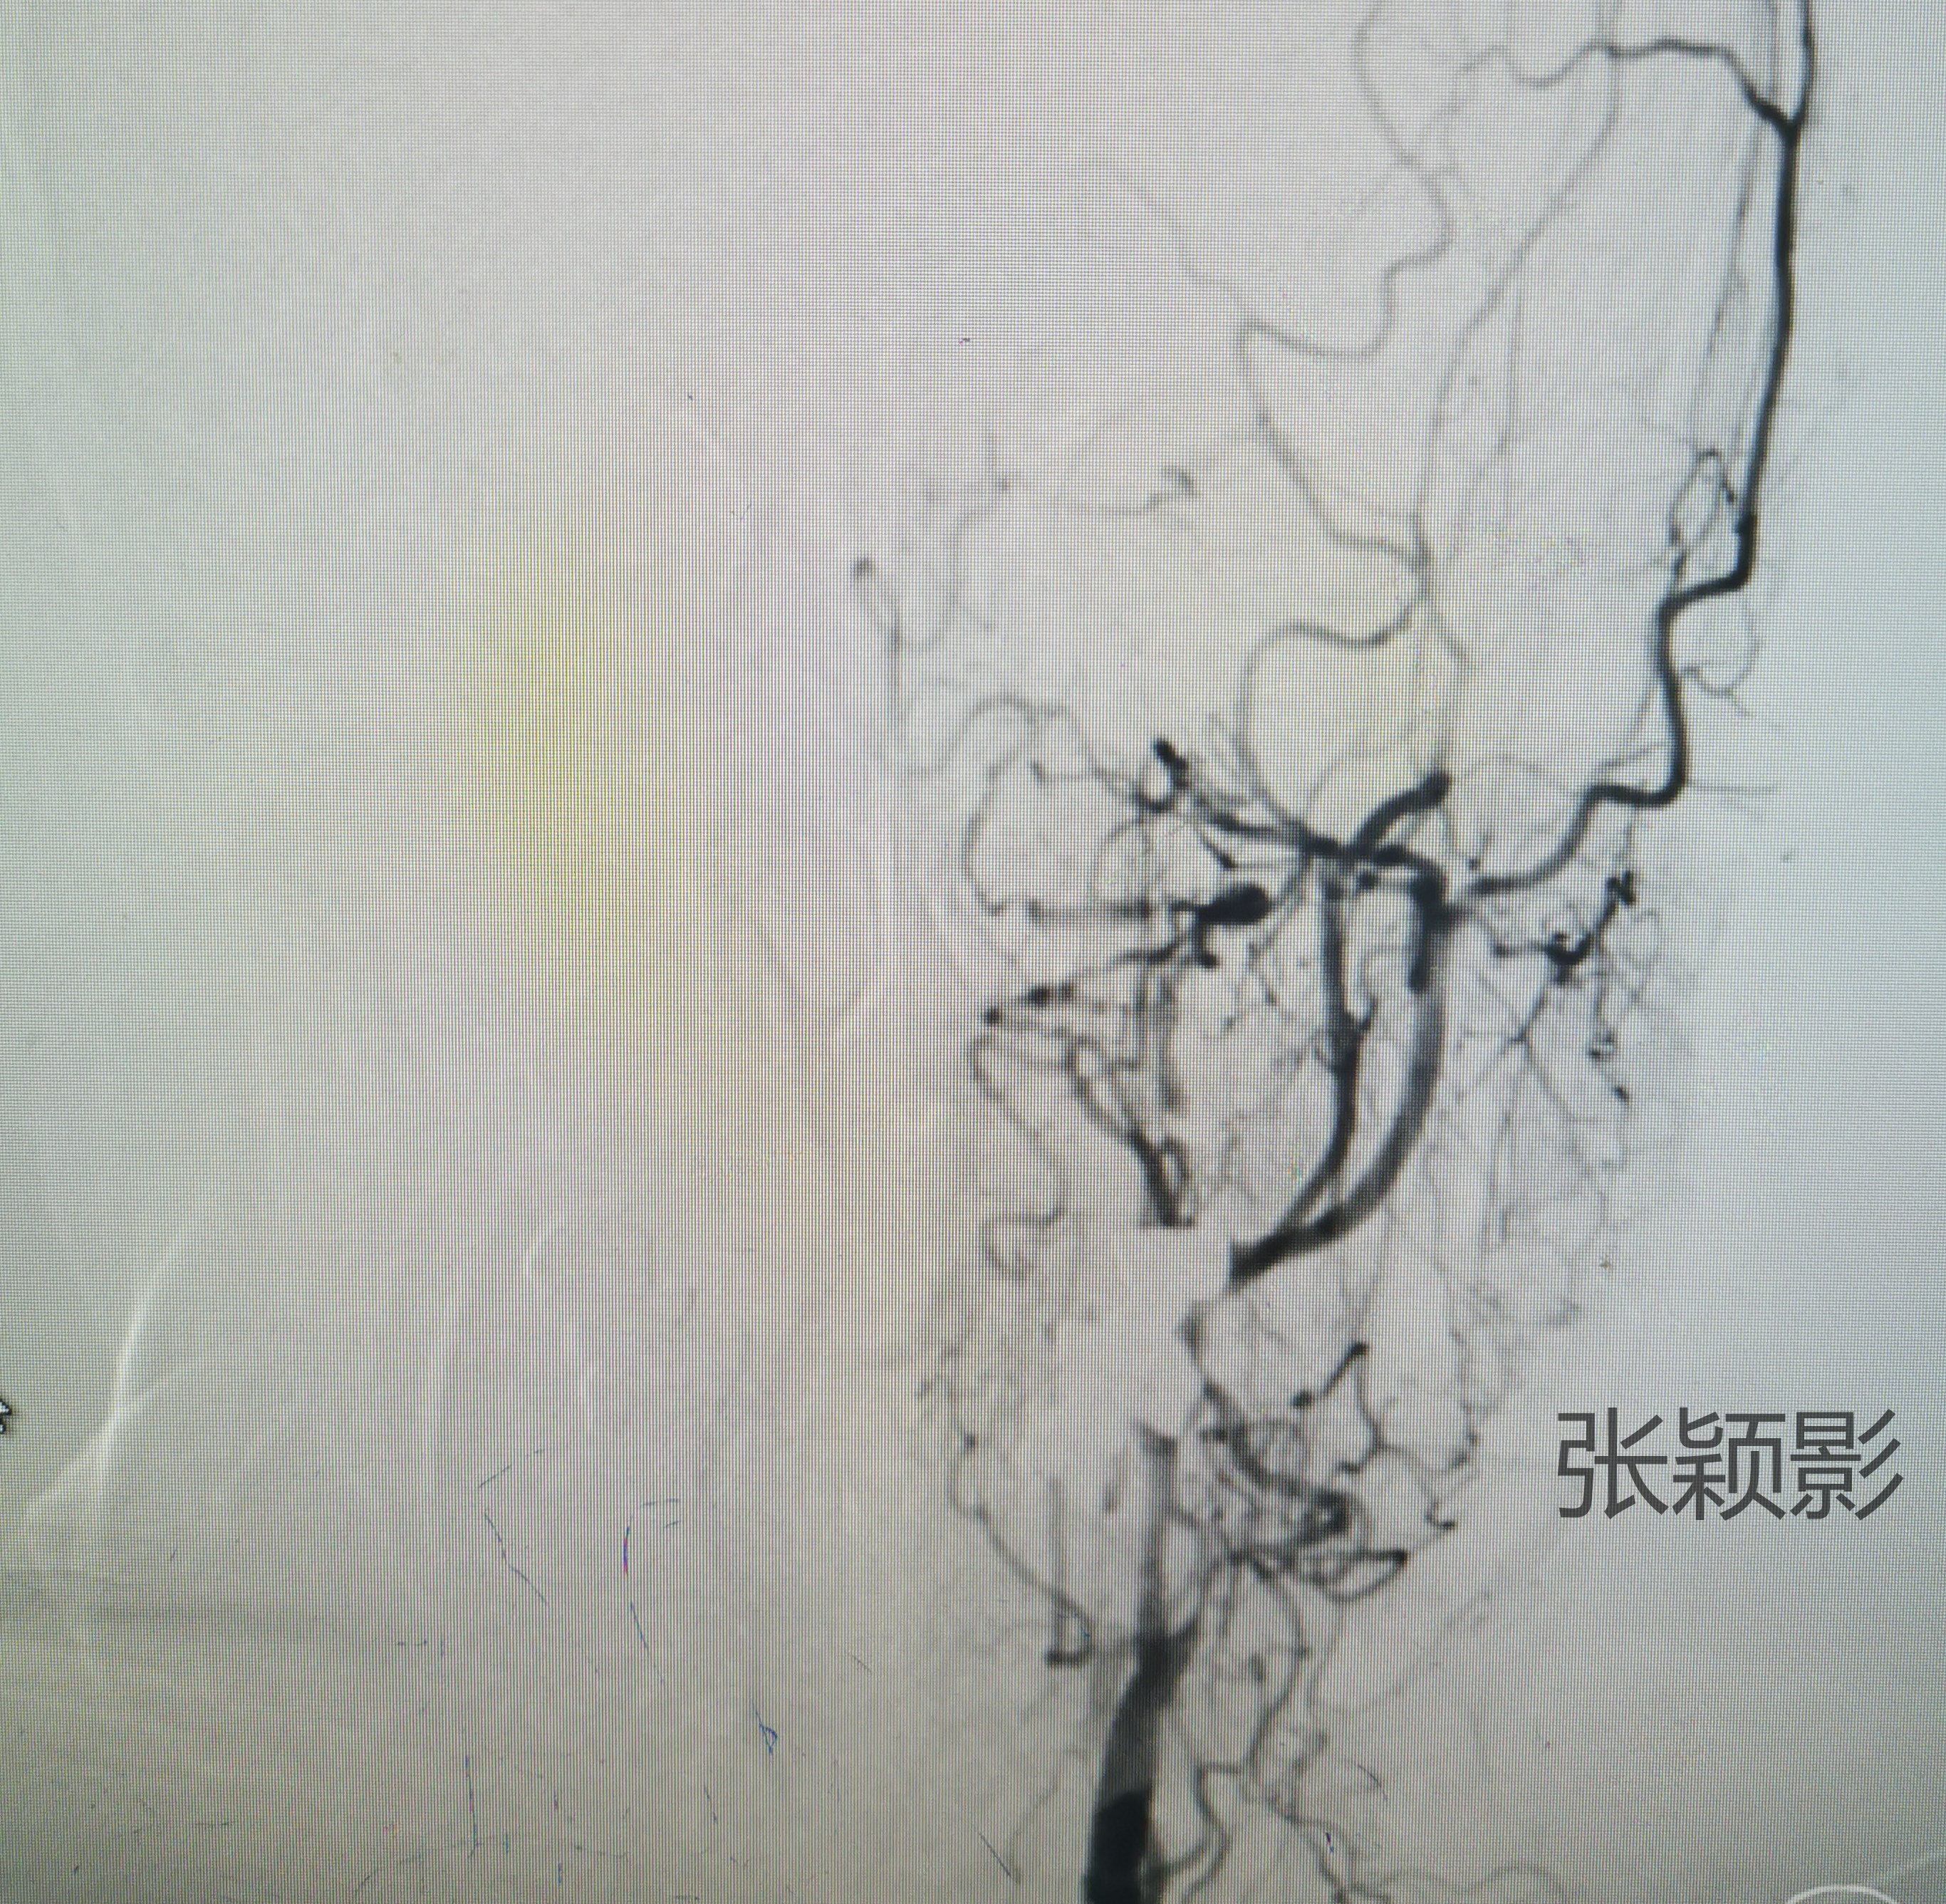

女性82岁,体检发现右侧大脑前动脉动脉瘤。正位造影提示动脉瘤位于右侧大脑前动脉A1段近段。